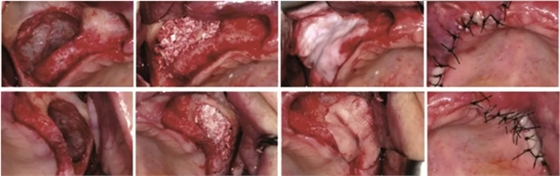

1、CGF/PRF作為屏障膜使用

在引導(dǎo)骨再生術(shù)中,需要使用可吸收或不可吸收的屏障膜,為骨組織的再生提供不受干擾的空間。如果使用CGF/PRF作為屏障膜,其相對(duì)目前臨床使用的可吸收生物膜是否具有優(yōu)勢(shì)?Gassling等進(jìn)行了一項(xiàng)臨床研究[4],研究納入了6例需要進(jìn)行雙側(cè)上頜竇外提升的患者,在完成植入骨替代材料后,一側(cè)使用PRF壓制而成的屏障膜覆蓋開窗處,而另一側(cè)則使用目前臨床廣泛使用的Bio-Gide生物膜覆蓋,如圖1示,以對(duì)比兩者的差異。作者發(fā)現(xiàn),術(shù)后患者兩側(cè)水腫、疼痛及初期創(chuàng)口愈合情況無明顯差異,術(shù)后5個(gè)月行種植體植入術(shù)時(shí),作者同時(shí)取出部分骨組織行組織學(xué)評(píng)估,發(fā)現(xiàn)兩組在新生骨的比例和骨替代材料的剩余比例上均無差異。

學(xué)者研究發(fā)現(xiàn),單獨(dú)使用CGF/PRF作為屏障膜,因?yàn)槠浣到馑俣容^快,無法達(dá)到理想的屏障效果。當(dāng)聯(lián)合生物膠原膜使用時(shí),未見明顯的促進(jìn)成骨效果,同時(shí)增加了手術(shù)費(fèi)用和手術(shù)難度。亦有學(xué)者表示CGF/PRF作為膜使用,聯(lián)合生物膠原膜應(yīng)用于GBR植骨術(shù)中時(shí),可以促進(jìn)局部軟組織的愈合,降低感染的幾率。